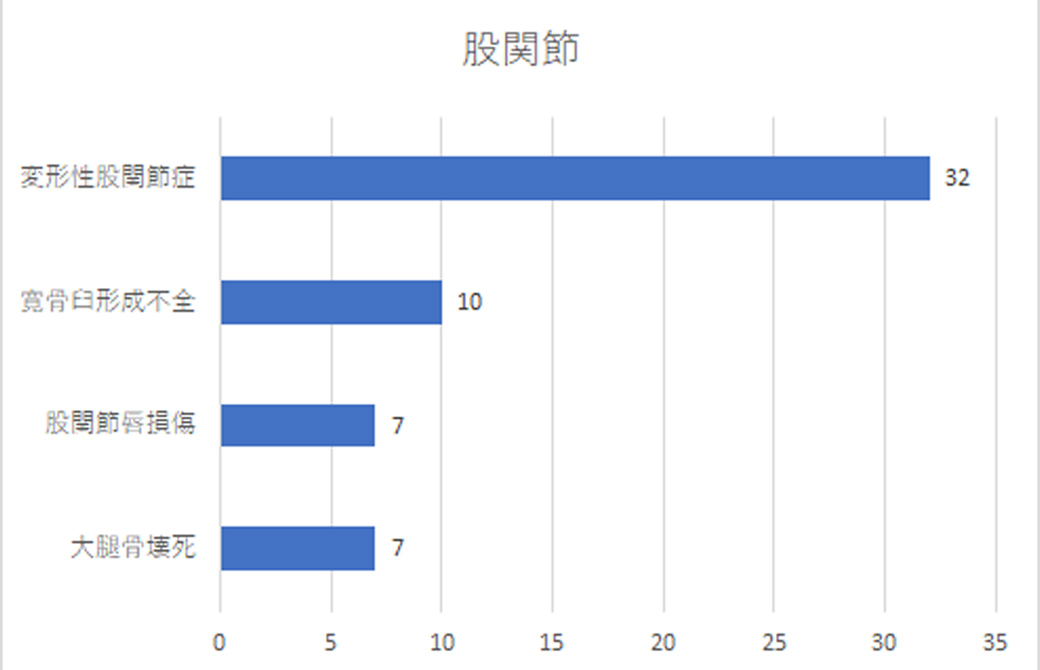

股関節|女性に多く見られる!?1位は変形性股関節症

股関節は、骨盤と大腿骨により構成される球関節。股関節の部門では、「変形性股関節症」が1位に。その他はどれも10票ほどという結果となりました。

この疾患の症状は、痛みと機能障害です。最初は「脚の付け根付近が痛い、何か違和感がある。」といったところから始まるようですが、次第に痛みが強くなり、長時間立つ・歩くが出来なくなったり、寝ている間も痛いということに。